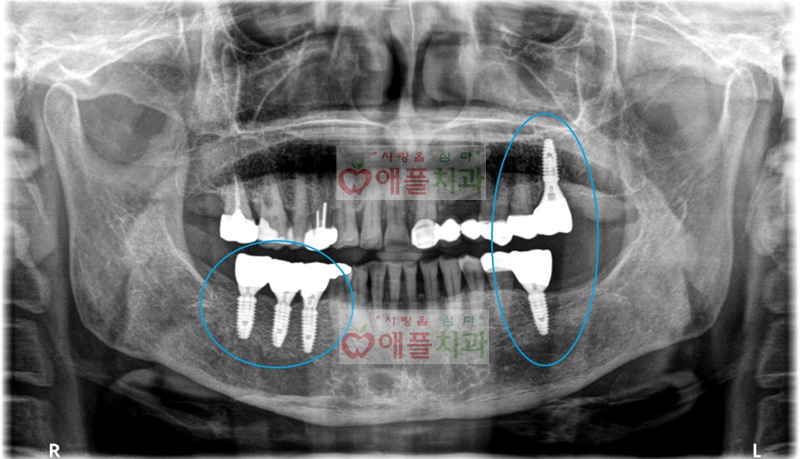

<보철 완성후 엑스레이>

현재까지 임플란트 수술한 부위에 특별한 불편감없이 잘 사용하고 계십니다.